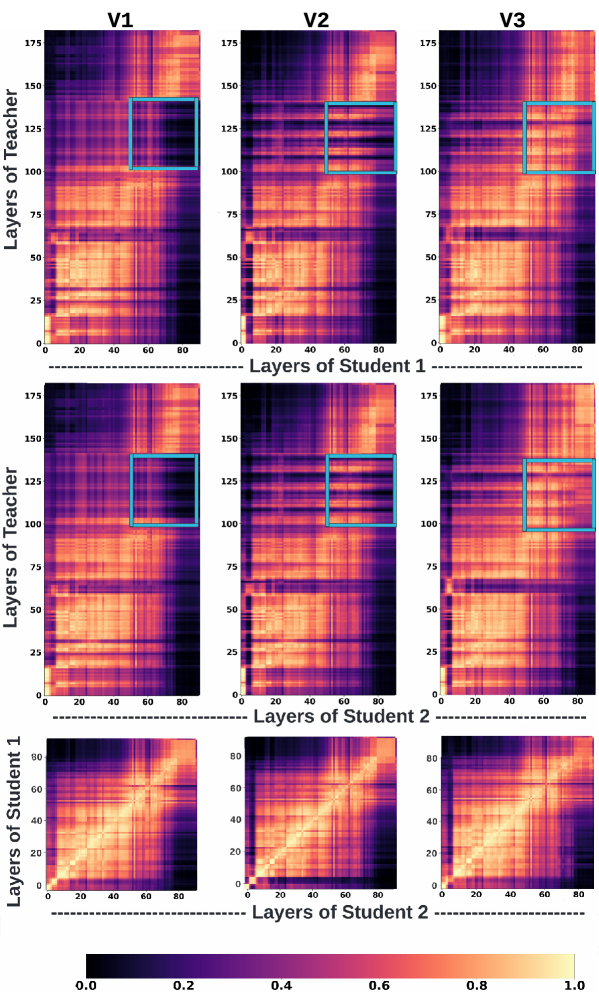

Finally, the improvement afforded by the knowledge diversification strategy is attributed to the increased similarity of learned representations between higher layers of the teacher and student networks as measured by the Centered Kernel Alignment (CKA) metric.

5.4 Explainability

To understand the effect of using different learning styles for the classification task, we used the popular Centered Kernel Alignment (CKA) metric [27] to measure and compare the similarity of learned representations of different layers of the teacher and student networks. As highlighted (blue box) in Figure 6, the CKA plots show increased similarity between the higher layers of the teacher and final layers of the student networks for the knowledge diversification paradigm (V3). As the deeper layers of a network are considered task-specific, this increased similarity could potentially explain the improved performance of KD + ML with V3 compared to all other knowledge distillation and sharing strategies (Figure 10 and 11 in the supplementary material). Finally, Figure 7 shows the ensemble segmentation masks of different knowledge-sharing models trained with the knowledge diversification paradigm (V3).